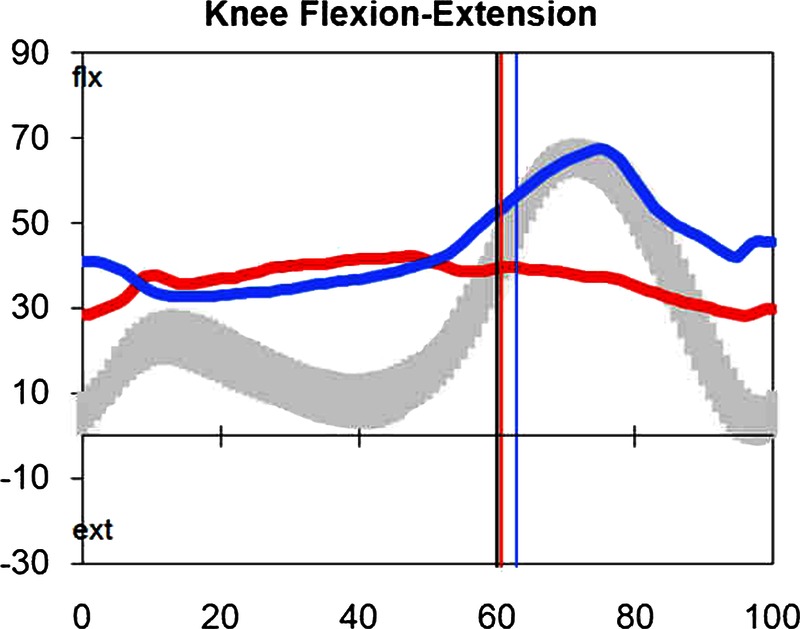

A 15-year-old boy with CP, Gross Motor Function Classification System (GMFCS) Level 2, attended our Gait Laboratory for repeat gait analysis due to a noted deterioration in his walking. His first analysis carried out 2 years earlier had identified bilateral knee crouch of 40° together with a stiff right knee and surgical intervention was recommended (figure 1). This was postponed due to other factors. The repeat gait analysis demonstrated bilateral knee crouch which was unchanged since the previous analysis; however, there was a noticeable lack of shock absorption and return to extension of the right knee, suggestive of extensor disruption. Radiography confirmed an incomplete fracture, greenstick fracture, of the anterior cortex of the right patella (figure 2).

Sagittal kinematics of both knees during a single gait cycle demonstrating midstance bilateral knee crouch (left—blue line and right—red line).